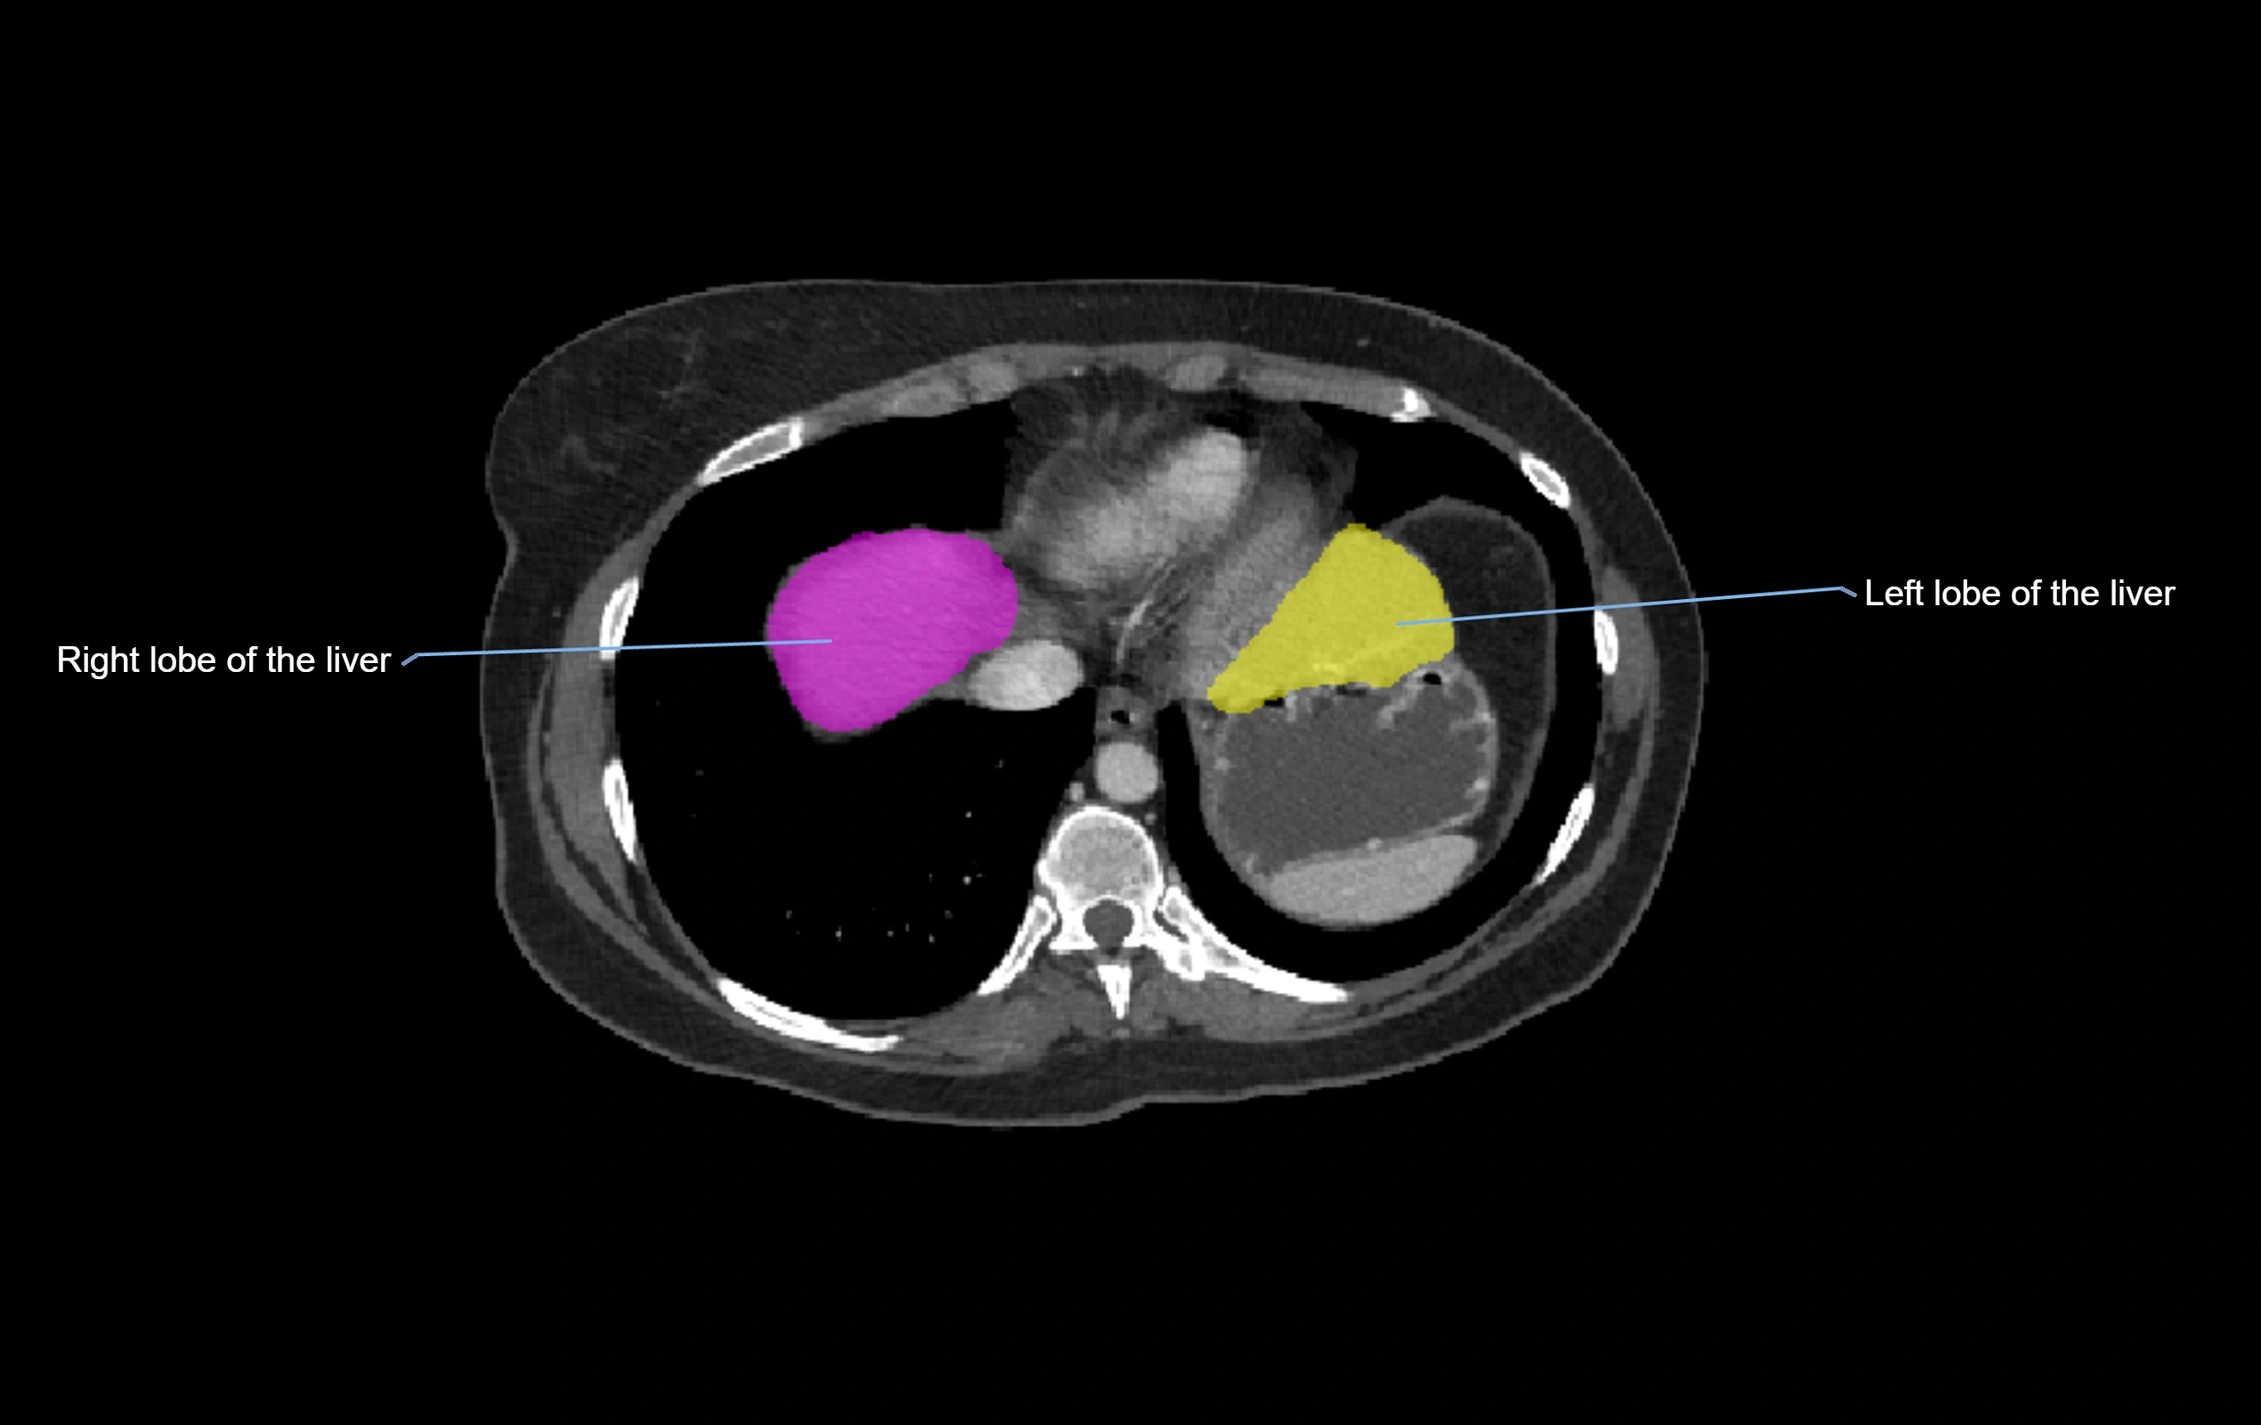

CT Appearance

CT Pre-Contrast:

• Caudate lobe appears as a soft-tissue density, isodense to the rest of the liver

• Enlargement may be appreciated in cirrhosis or Budd–Chiari syndrome

CT Post-Contrast:

• Homogeneous enhancement in the portal venous phase, similar to rest of liver

• Independent venous drainage into the IVC may be visualized

• Lesions follow characteristic CT enhancement patterns (HCC: arterial hyperenhancement with washout; hemangiomas: peripheral nodular enhancement with centripetal fill-in)

CT Venous Phase (functional significance):

• Caudate lobe often enhances relatively more than other lobes in Budd–Chiari syndrome, due to preserved venous outflow